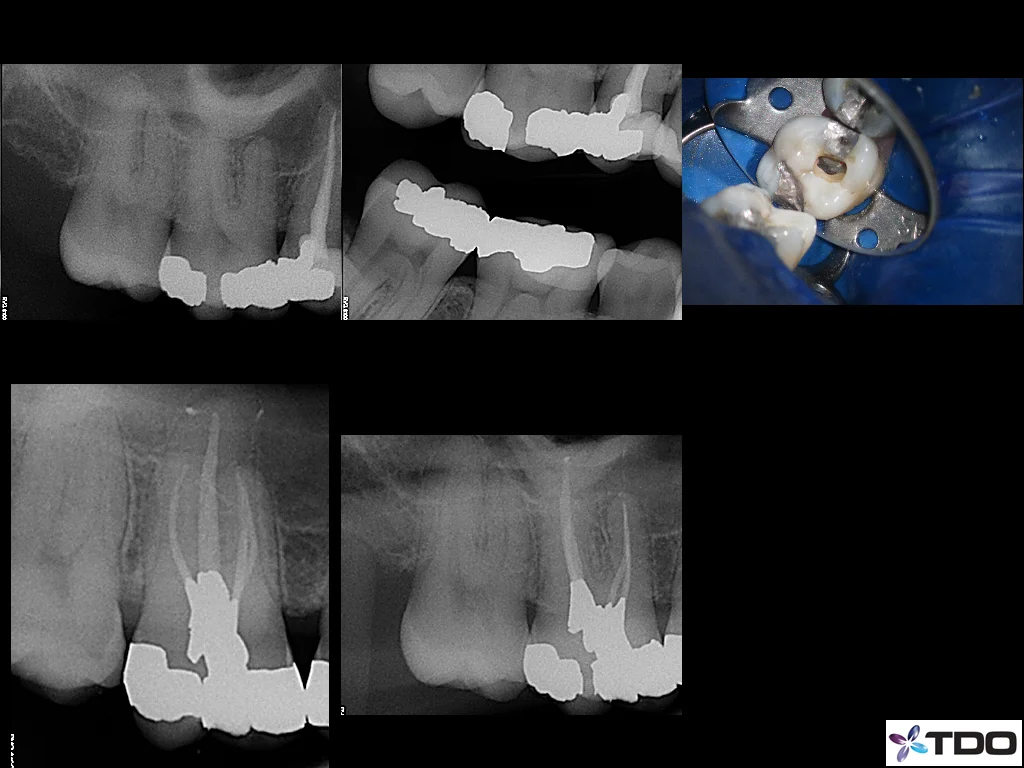

This recently coined term refers to a concept of providing endodontic therapy while maintaining the maximal amount of tooth structure. Traditionally, dentists and endodontists were trained to open the roof of the tooth chamber to provide "straight line access" to all canals - which can significantly weaken the tooth. This was necessary prior to the advent of the modern endodontic armamentarium. The improved visualization and ergonomics provided by the microscope and the flexibility of today's rotary endodontic files allows us complete ideal endodontic therapy while minimizing the amount to coronal tooth structure removal. This minimalist idea can be extended to the root canals themselves. Most recent endodontic literature has been geared toward a "bigger is better" idea of cleaning and shaping. While there is little doubt that this methodology will lead to a "cleaner" canal, what is less clear is whether this "increased cleanliness" improves the long-term success. Interesting, endodontic success rates have not risen significantly in recent years. This would at least raise the possibility that "bigger/cleaner" may not matter in the way that we have been trained. Our goal is simply to treat the patient's symptoms/disease while respecting the dentin (especially the pericervical dentin). This method does not create "the look" of the dramatically tapered root canal preparations that are seen in most of today's endodontic marketing material; however, it should lead to improved long-term success and tooth retention. The cases below illustrate how this concept has been implemented into our practice.

Coronal endodontics (Permanent access Restoration):

If at all possible, we try to place the coronal restoration on all teeth on which we perform root canal therapy. This ensures that there is no contamination of the obturated canals prior to the patient's returning to your office, as the final restoration is placed under rubber damn isolation. Having just completed the case, we have intimate working knowledge of the root anatomy and can place the most appropriate restoration.